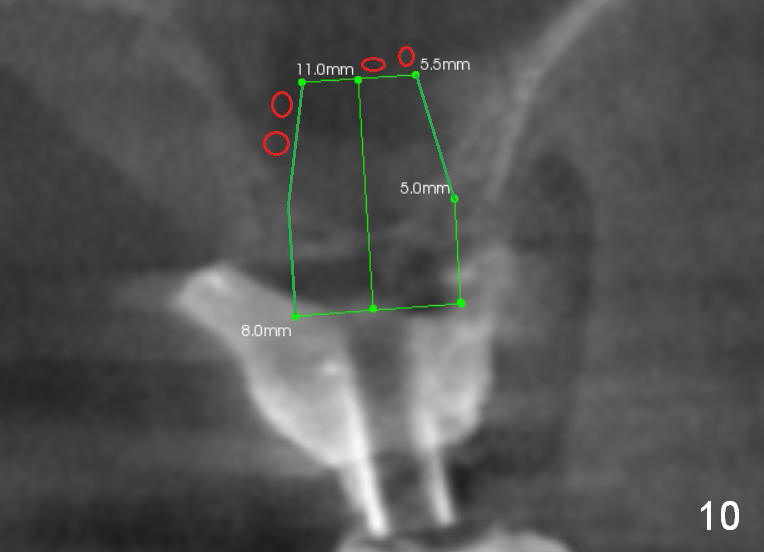

After crestal incision, a 3.5 or 4 mm trephine bur is used for 2 mm at #14. The regional sinus floor is lifted using a Bicon flat-end osteotome, followed by bone graft and taps. If the 6x11 mm tapered tap does not gain stability (Fig.3), use either 6x11 mm round tap (Fig.4) or 7 or 8x11 mm tapered tap (Fig.5). If the last does not work, try a larger round tap (Fig.6). In all, the sinus floor is pushed upstairs and an implant is inserted to be engaged into the sides of the sinus floor (Fig.7).

Coronally, a round implant does not appear to obtain more bone contact than a tapered one of the same diameter (Fig.8,10). Internal sinus lift works for this case?